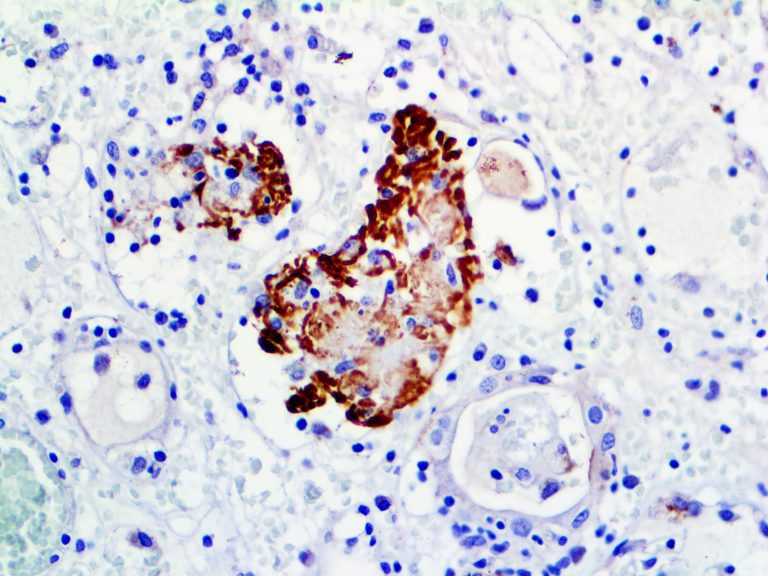

It is the ICU physician who is most likely to witness one of the deadliest manifestations of the abnormal immunological response, the cytokine storm syndrome (CSS). This response is also referred to by some as the cytokine release syndrome (CRS). CSS is characterized by continuous activation and expansion of macrophage and lymphocyte populations, which secrete large amounts of cytokines, causing the cytokine storm. This massive cytokine release is akin to hemophagocytic lymphohistiocytosis (HLH) disease, a syndrome characterized by initial unchecked and persistent activation of cytotoxic T lymphocytes and NK cells.

Clinical and laboratory manifestations of HLH include fever, enlarged liver and/or spleen, neurologic dysfunction, coagulopathy, liver dysfunction, cytopenias (i.e., low levels of erythrocytes, leukocytes, and/or platelets), hypertriglyceridemia, hyperferritinemia, hemophagocytosis, and eventually diminished NK cell activity as the immune system becomes progressively paralyzed. HLH can be familial (primary HLH) or secondary to another disease process (sHLH), such as rheumatic disease, in which it is referred to as macrophage activation syndrome (MAS, characterized by elevated ferritin).